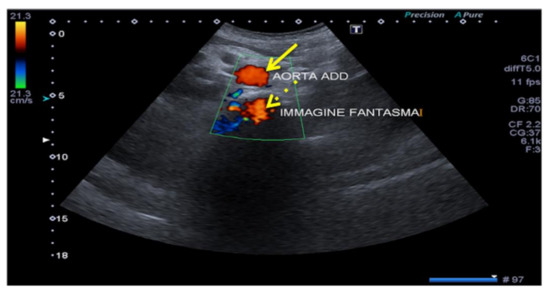

3.1.2. The Mirror-Imaging Effect

When the US of the primary incident beam passes through a curved interface with high specular reflection capacity (e.g., the diaphragm), the structure close to this interface can be reproduced on the US image both in its real position and in a symmetrical opposite position, beyond the reflecting surface (e.g., mirror image of the liver, which can be mistaken for a parenchymal consolidation, or the aorta, which can produce a “ghost image”) (Figure 3, Figure 4 and Figure 5). Mirror-image artifacts will disappear when the reflector is scanned with oblique orientation [5,6].

Figure 5. Aorta ghosting. Transverse mesogastric color-Doppler US image obtained at the level of the infra-renal aorta (arrow) shows aorta ghosting (dashed arrows) that projects backwards with the same color sign.